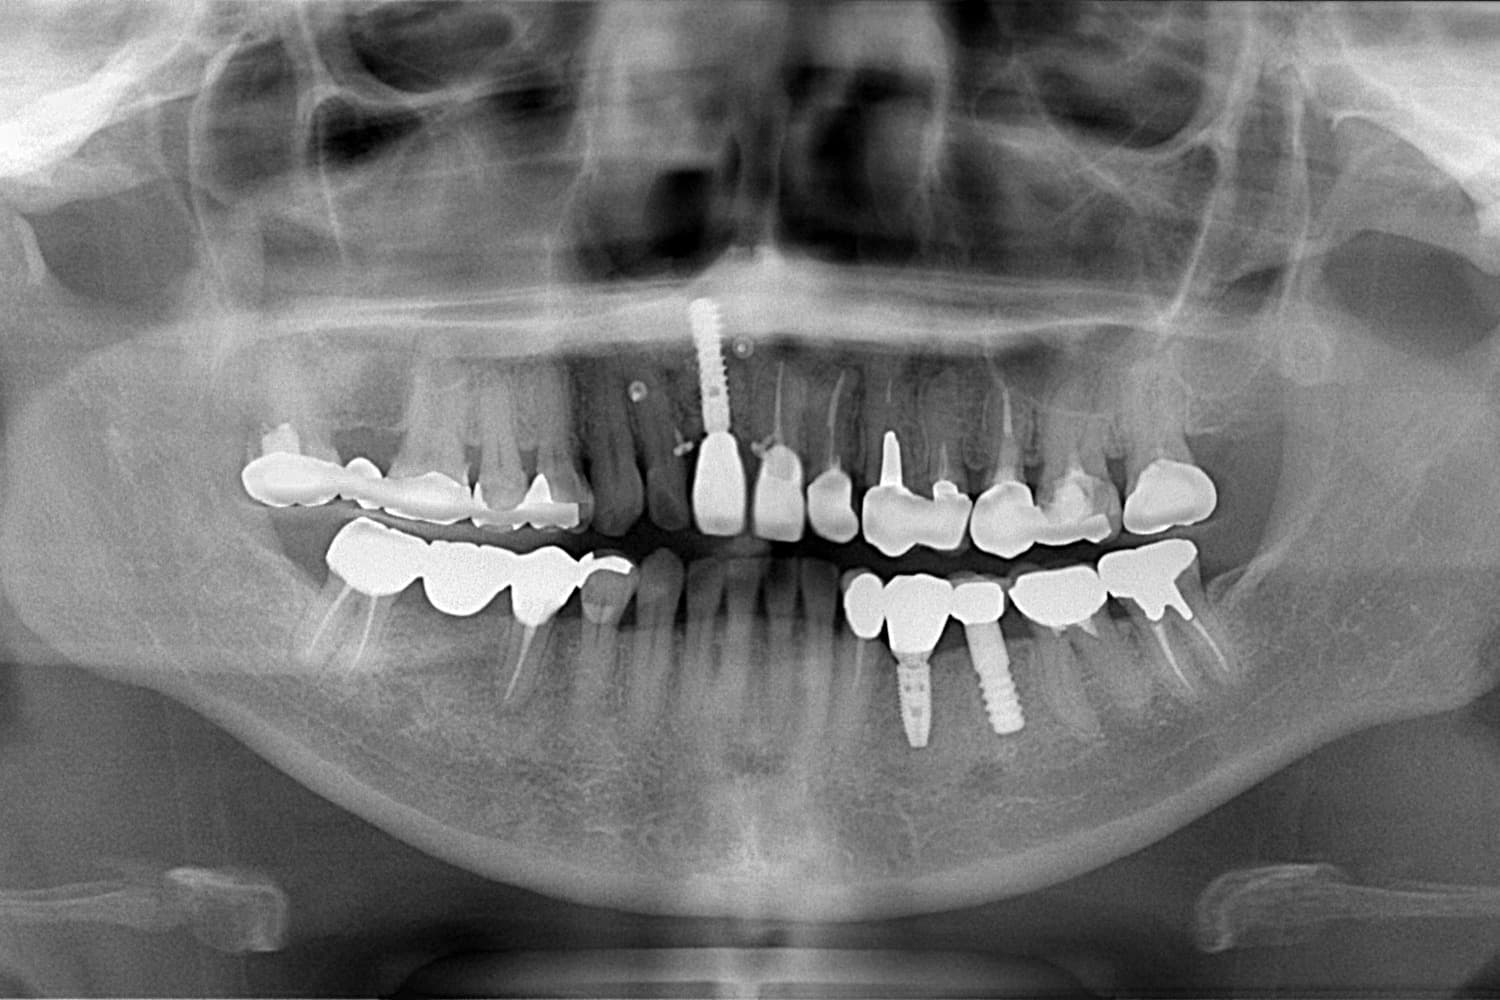

右上1の前歯部のインプラント治療

Before

After

年齢

50代

性別

女性

主訴

前歯を綺麗にしたい

治療期間

10カ月

治療回数

15回

費用

913,000円

副作用・リスク

清掃状態等によりインプラント周囲に炎症を起こす可能性があります。